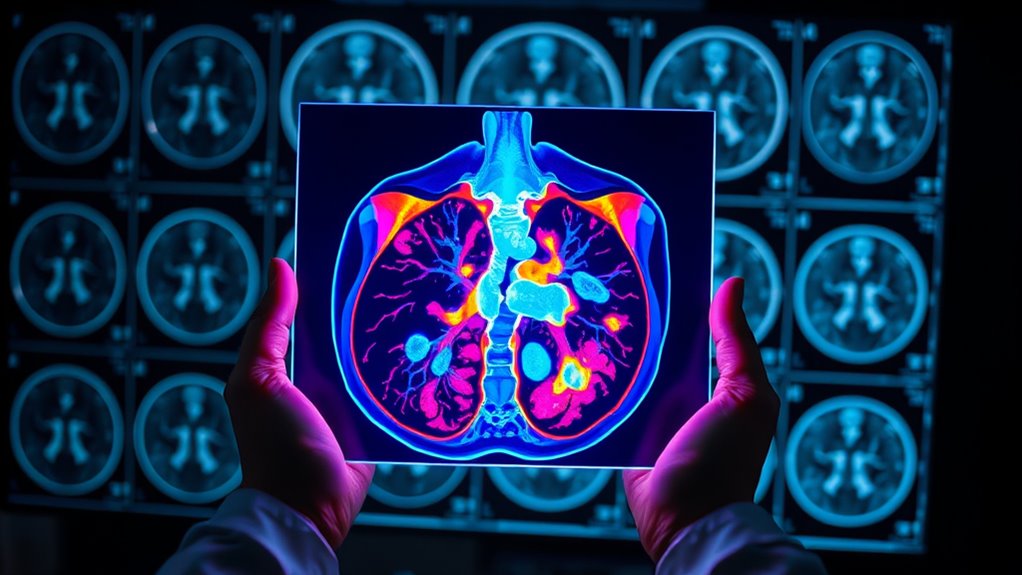

Wie PET/CT funktionale und strukturelle Einblicke kombiniert

PET/CT kombiniert nahtlos funktionale und strukturelle Informationen und bietet einen umfassenden Blick auf Krebs. PET zeigt, wie aktiv der Tumor ist, indem es die Aufnahme von Radiotracern nachweist, was die metabolischen Prozesse widerspiegelt. Gleichzeitig zeigt CT die genaue Lage und Größe des Tumors und bietet detaillierte Anatomie. Die Kombination dieser beiden Verfahren ermöglicht eine präzise Bestimmung von Tumoraktivität und -struktur gleichzeitig. Diese Fusion verbessert die Biopsie-Targeting und hilft dabei, benigne von malignen Läsionen zu unterscheiden, wenn andere bildgebende Verfahren an ihre Grenzen stoßen. Sie können kleine oder nekrotische Tumoren besser lokalisieren, was die Behandlungsplanung verbessert. Die folgende Tabelle hebt die wichtigsten Aspekte dieser Integration hervor:

Radiotracer spielen eine entscheidende Rolle bei der Verbesserung der Fähigkeiten des PET-Scannings, indem sie die Stoffwechselaktivität innerhalb von Tumoren hervorheben. Sie erhalten typischerweise einen Radiotracer wie FDG, der von Krebszellen aufgrund ihres höheren Glukosemetabolismus aufgenommen wird. Nach der Injektion sendet der Tracer Positronen aus, die vom PET-Scanner erkannt werden, was eine Visualisierung der aktiven Tumorregionen ermöglicht. Die Fusion mit CT bietet eine präzise anatomische Lokalisation, was die Identifizierung bösartiger Läsionen erleichtert. Radiotracer ermöglichen es Ihnen, zwischen benignen und malignen Geweben zu unterscheiden, kleine oder sonst verborgene Metastasen zu erkennen und die Tumoraggressivität zu beurteilen. Ihre Fähigkeit, biologisch aktive Bereiche sichtbar zu machen, bietet wertvolle Einblicke in Tumorverhalten und die Reaktion auf Therapien, was PET-Scans zu einem leistungsstarken Werkzeug in der Krebsdiagnose, Stadieneinteilung und Behandlungsplanung macht. Darüber hinaus helfen Fortschritte in predictive analytics dabei, die Interpretation von PET-Daten zu optimieren, was die diagnostische Genauigkeit verbessert und personalisierte Behandlungsansätze fördert.